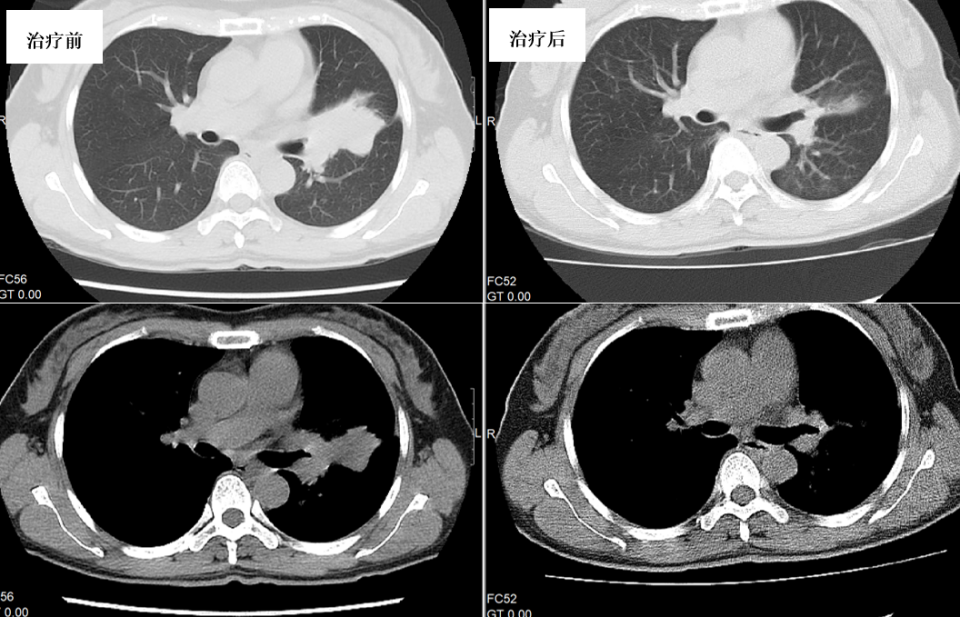

胸部CT(图6):左上肺舌段不张并多发病灶。腰椎MRI示:腰1、2椎体、腰4棘突异常信号。

图6. 治疗5个月后左上肺舌段病灶较前明显缩小